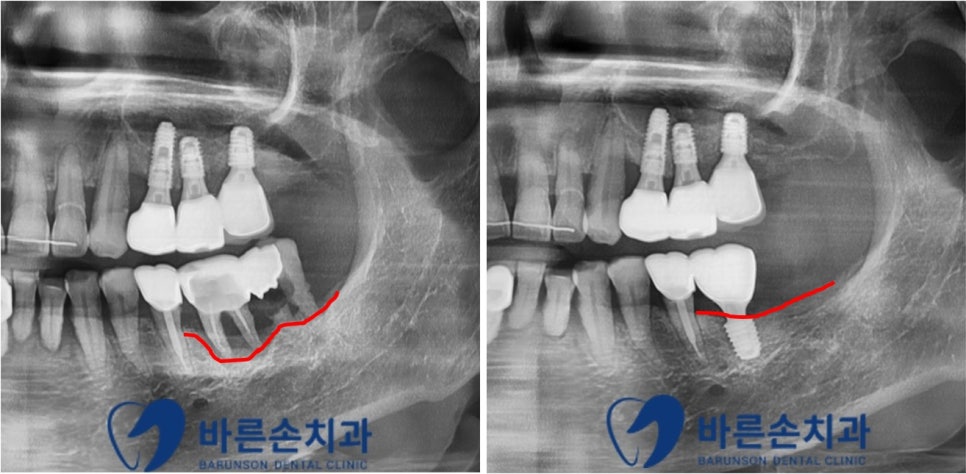

치료 전 치료 후

치료 전후 사진의 치조골의 높이를 표시한 붉은 선을 보시면

치료 전 염증으로 인해 손상되었던 치조골이

뼈이식과 임플란트 수술을 통해 복구가 된 것을 확인할 수 있습니다